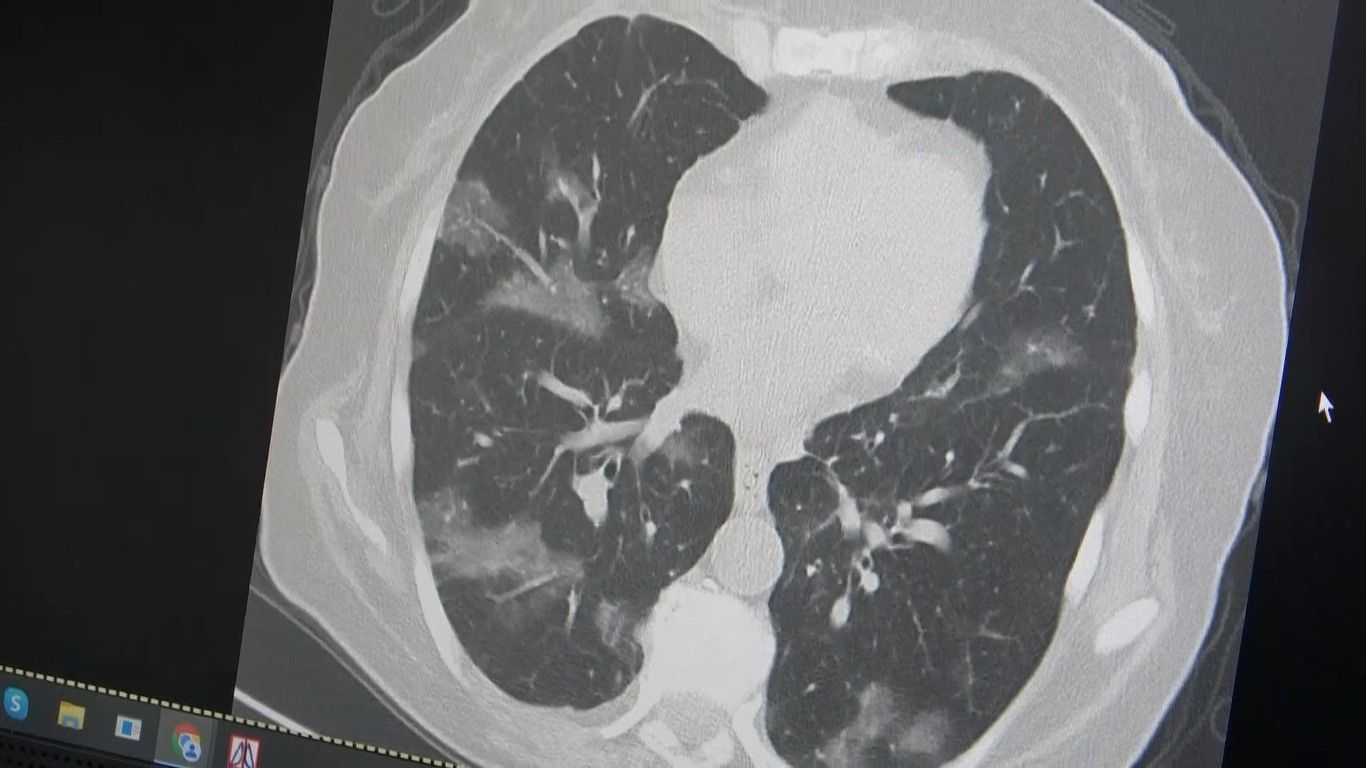

Öksürüğünüz bir türlü geçmiyor. Tam adına uygun bir şekilde flört eder gibi dalgalanmalarla seyrediyor. Son günlerde özellikle Kovid-19'un ilk başında gördüğümüz vakalar gelmeye başladı. İlk başlarda akciğer tutulumlar çok görüyorduk. 2024 yılı başından itibaren neredeyse hiç akciğer tutulumu görmemiştik ama bu son günlerde vakalar gelmeye başladı. Özellikle kanser hastaları risk altındadır. Kemoterapi alan, vücut direnci düşük kişiler akciğer tutulumu ile geliyorlar. Özellikle yurt dışı tatilinden ve hacdan dönen kişilerin yaşlı ve vücut direnci düşük kişilerle bir araya gelmesini önermiyoruz” şeklinde konuştu.

Kanser hastası bir kişinin akciğerleri üzerinde örnek veren Özkaya, “60 yaşının üstünde olduğu ve kemoterapi aldığı için virüsün kolayca ciğerlere indiğini görüyoruz. Bu yaza damgasını vuracak yeni virüsün bu olduğunu düşünüyoruz” ifadelerini kullandı.